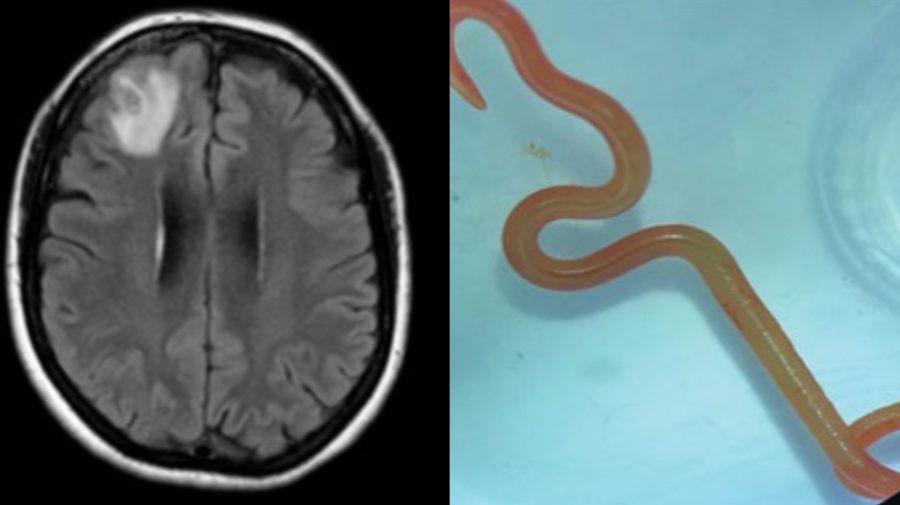

Nakoniec žena začala trpieť aj depresiami a zábudlivosťou, a to ju doviedlo do nemocnice v Canberre. Keď ju neurológovia začali operovať, netušili, že jej v mozgu nájdu živého parazita. Keď však červa našli, narýchlo sa radili s kolegami, čo urobiť ďalej.

Ophidascaris robertsi je červ, ktorý sa zvyčajne vyskytuje v telách pytónov kobercových. Dáma z Austrálie, v ktorej mozgu sa parazit vyskytol, je prvým zdokumentovaným prípadom výskytu v človeku v histórii.

Problémy ale neskončili identifikáciou parazita. Keďže išlo o prvý prípad v histórii, doktori museli stanoviť jej liečbu úplne od nuly. Čelili pri tom obavám, pretože niektoré lieky môžu napríklad vyvolať zápal, keď larvy odumierajú. Zápal by mohol byť škodlivý pre orgány, akými je napríklad mozog. Doktori preto museli myslieť aj na lieky, ktorými by potlačili vedľajšie účinky.